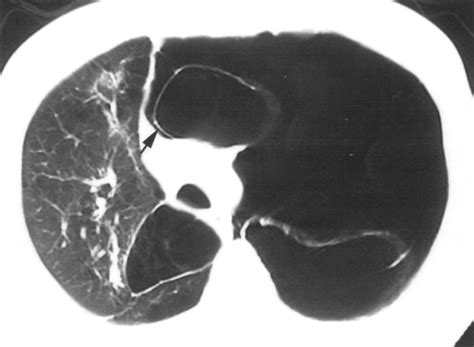

⚠️ Note: Always consult with a pulmonologist to undergo diagnostic imaging, such as a CT scan, as chest X-rays may not always reveal the full extent of the bullae.

Diagnostic Procedures

Diagnosis begins with a thorough medical history and physical examination. However, imaging is essential to confirm Bullous Lung Disease. High-resolution Computed Tomography (HRCT) is considered the gold standard for visualizing bullae. It allows physicians to determine if the bullae are localized or widespread and whether they are compressing functional lung tissue. Pulmonary function tests (PFTs) are also conducted to measure lung capacity and identify the degree of airflow obstruction.